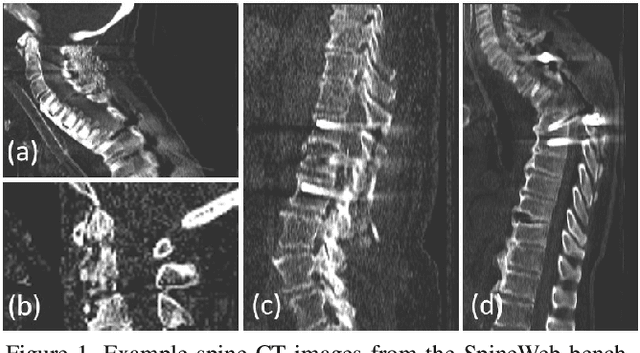

Abstract:Accurate vertebra localization and identification are required in many clinical applications of spine disorder diagnosis and surgery planning. However, significant challenges are posed in this task by highly varying pathologies (such as vertebral compression fracture, scoliosis, and vertebral fixation) and imaging conditions (such as limited field of view and metal streak artifacts). This paper proposes a robust and accurate method that effectively exploits the anatomical knowledge of the spine to facilitate vertebra localization and identification. A key point localization model is trained to produce activation maps of vertebra centers. They are then re-sampled along the spine centerline to produce spine-rectified activation maps, which are further aggregated into 1-D activation signals. Following this, an anatomically-constrained optimization module is introduced to jointly search for the optimal vertebra centers under a soft constraint that regulates the distance between vertebrae and a hard constraint on the consecutive vertebra indices. When being evaluated on a major public benchmark of 302 highly pathological CT images, the proposed method reports the state of the art identification (id.) rate of 97.4%, and outperforms the best competing method of 94.7% id. rate by reducing the relative id. error rate by half.